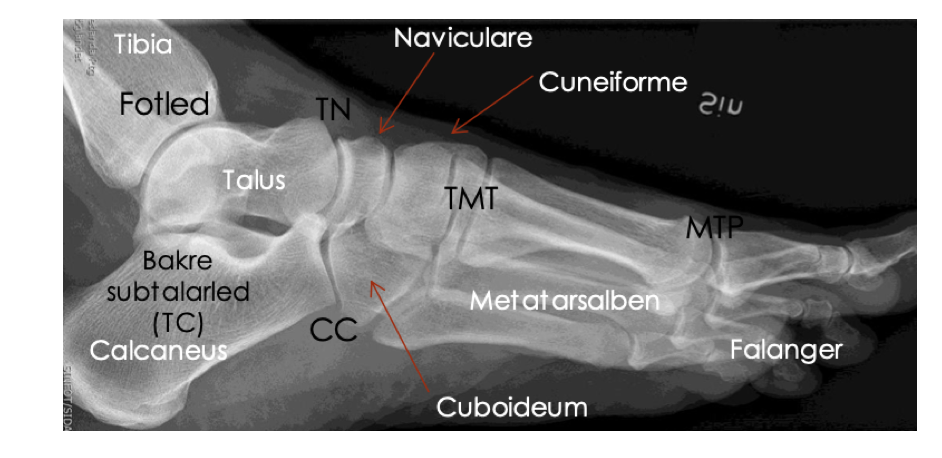

anatomi fot från sidan

vad heter alla leder i benet?

Subtalarleder

NC-leder = naviculare-cuneiforme-led

TMT-leder = tarsometatarsallederna

Stortåns grundled: MTP1 = metatarsofalangealled 1